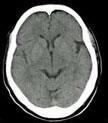

CT検査

CT検査は種々の角度からX線を照射し、人体を通過したⅩ線量を測り、コンピュータを使って輪切り断面を画像化する検査です。ベッドの上に横になって頂き、大きなドーナツ型の機械に入っていきます。検査時間は、撮影部位や内容により異なりますが、5~15分程度です。MDCTと呼ばれる最近の装置では、一回転で複数の断面の情報を得ることができるため、広範囲の細かな病気の画像を短時間で得ることができるようになりました。

当院では256列、64列が2台の計3台のCTが稼働し、予約検査のみならず当日検査や緊急検査、心臓CT、肺検診などにも対応しています。